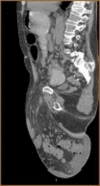

We report a case of a giant inguinal hernia (GIH) that underwent open surgical repair with mesh. The patient had a massive transcompartmental redistribution of abdominal contents from the abdominopelvic cavity to the hernia sac in the scrotum, with subsequent effects on the mechanical nature of the abdominal wall muscles. Repair of this type of giant hernia is challenging as it can raise the intra-abdominal pressure, therefore increasing the risk of abdominal compartment syndrome (ACS). The large size and chronicity of the hernia, associated with deranged mechanical forces/properties of the abdominal wall, made the management of this complex case unique and interesting. In similar cases of massive incisional or ventral hernias, the term "loss of domain" (LOD) is used. In such types of massive hernias, it is important to carefully plan and monitor for adverse physiological effects associated with increased abdominal pressure.